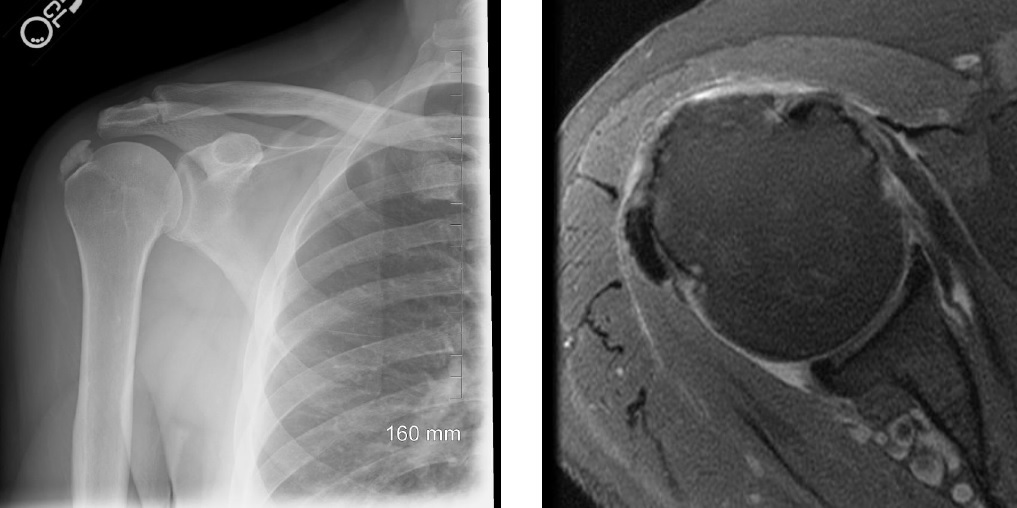

calcific tendonitis

Crest Syndrome